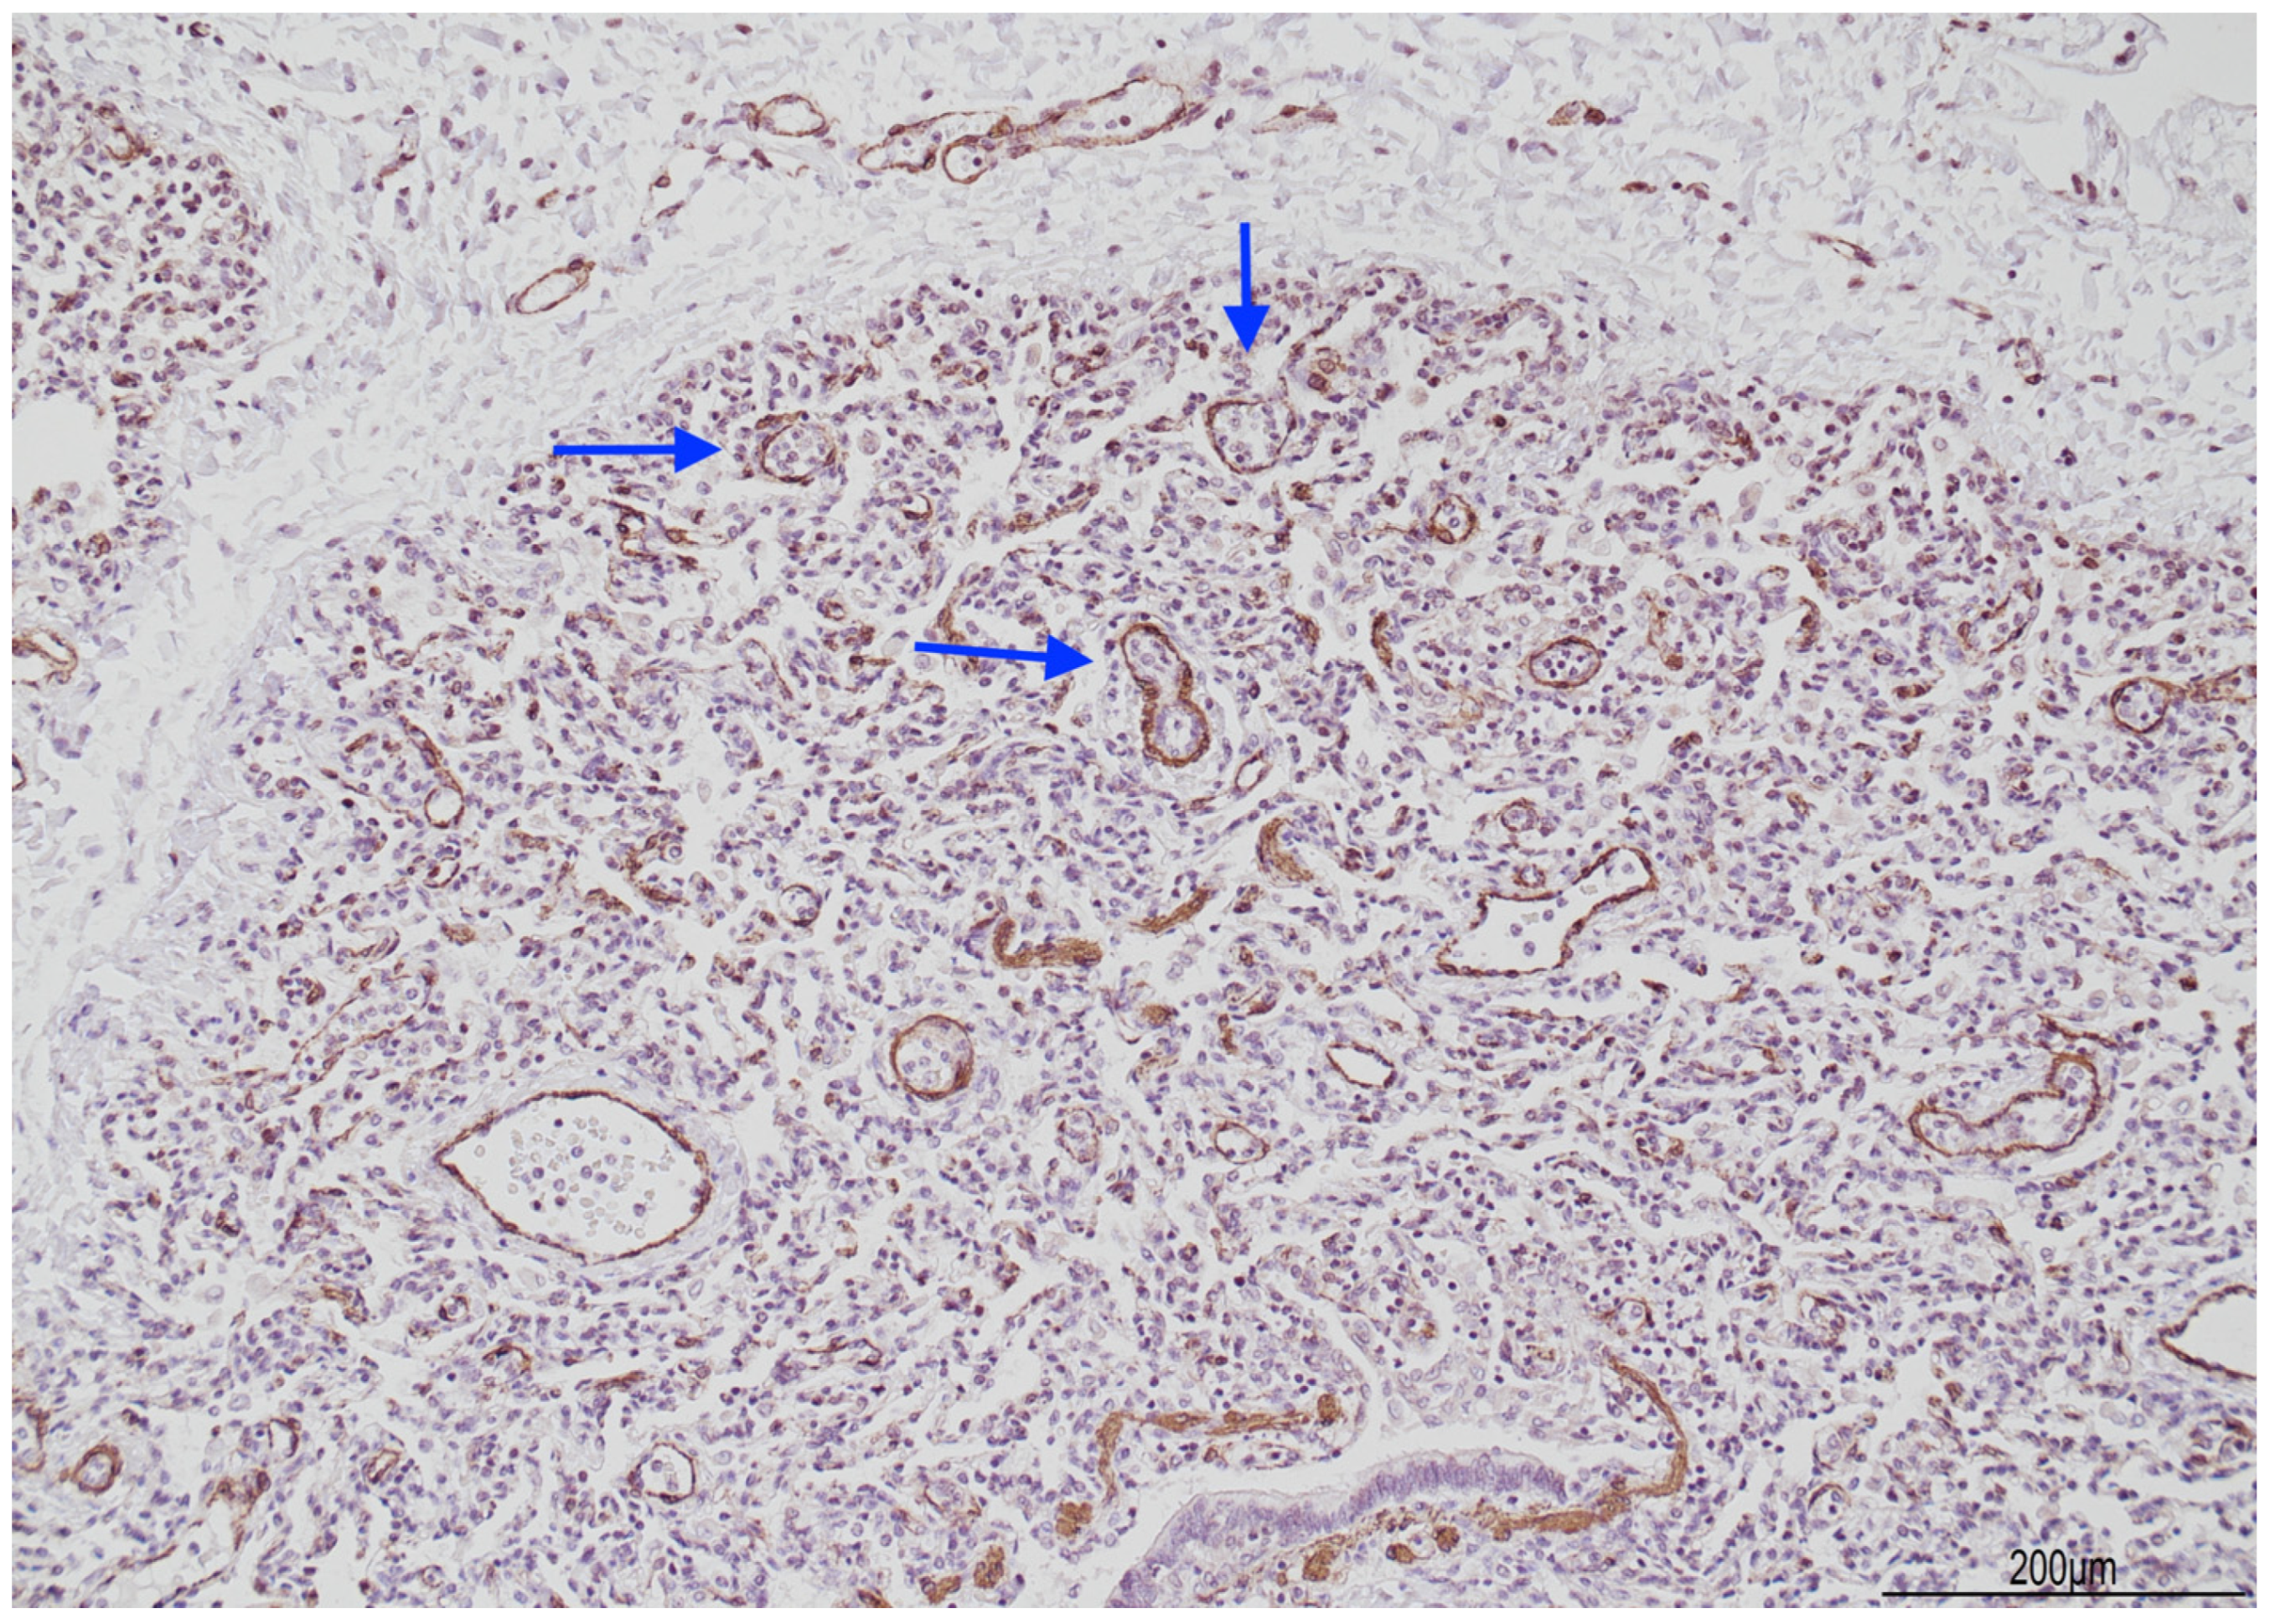

2.3. Histological Findings

3. Discussion